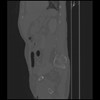

7 CUERPO,CE,Sagittal,3.000,CUERPO,Sagittal,